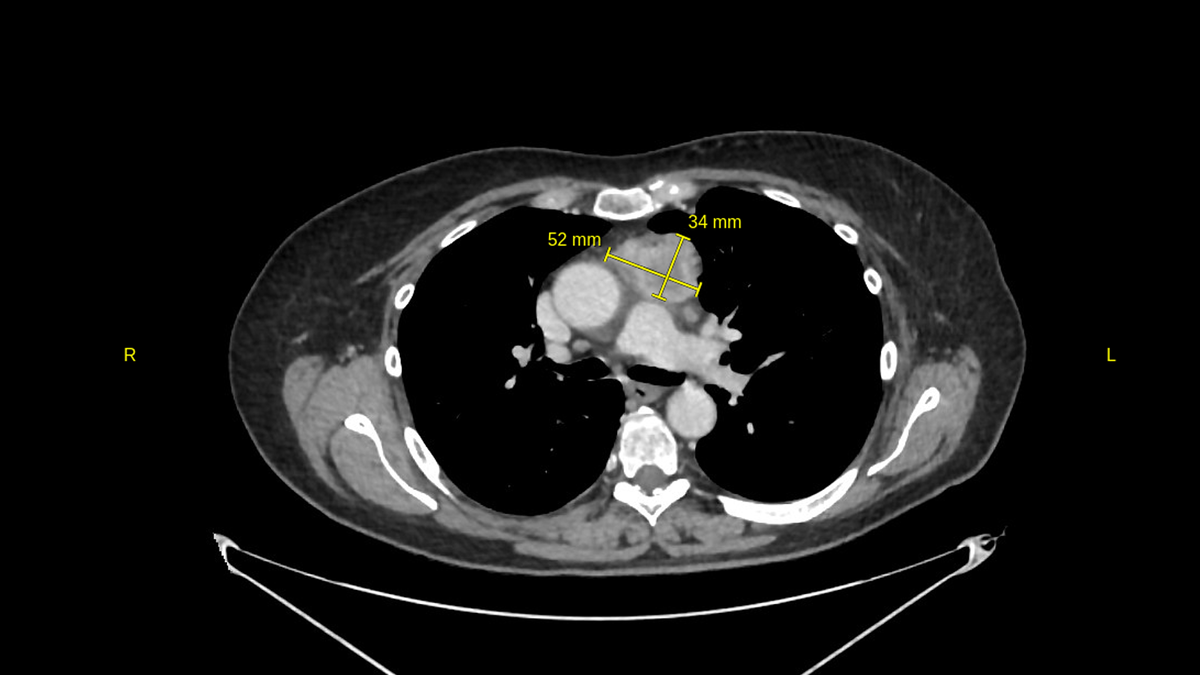

В нашем центре была выполнена компьютерная томография грудной полости, брюшной полости и малого таза с внутривенным контрастированием. И вот, что мы увидели на снимках.

...в переднем верхнем средостении определяется объемное образование, неправильной округлой формы, без четких контуров, кистозно-солидной структуры, размерами до 52х34 мм в поперечнике и высотой до 45 мм...